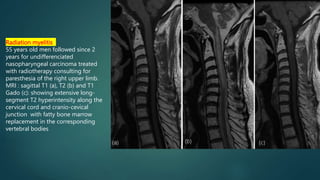

Radiation myelitis

55 years old men followed since 2

years for undifferenciated

nasopharyngeal carcinoma treated

with radiotherapy consulting for

paresthesia of the right upper limb.

MRI : sagittal T1 (a), T2 (b) and T1

Gado (c): showing extensive long-

segment T2 hyperintensity along the

cervical cord and cranio-cevical

junction with fatty bone marrow

replacement in the corresponding

vertebral bodies